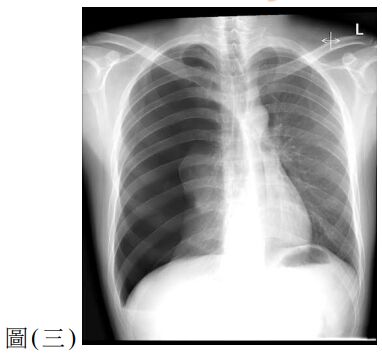

12. 一位 25 歲男性因呼吸困難至急診就醫,主訴 2 天前工作撞擊到右側胸部,胸部 X 光檢查如圖 ( 三 ) ,下列處置何者較適當? (A) 立即給予右側胸管置入引流 (B) 觀察呼吸困難狀況並給予肌肉鬆弛劑 (C) 立即安排胸腔鏡手術治療 (D) 安排胸部電腦斷層檢查確立診斷